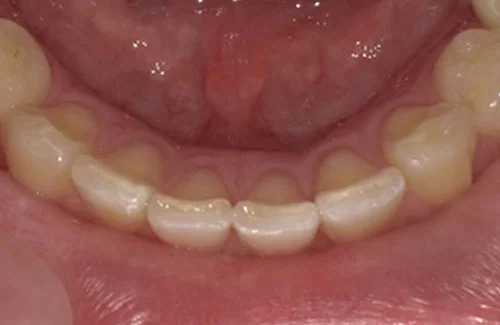

<症例7>歯がガタガタで噛み合わせが悪くお悩み

抜歯無し・マウスピースのみで矯正した症例です。

もともと歯列弓が非常に狭く、V字に近い形をしていたので噛み合わせも非常に不安定でした。

また、下顎前歯部がかなり上の方に生えていたため、下の前歯が上の前歯を突き上げてしまい出っ歯の状態になっていました。

現在では見た目はもちろん、臼歯の噛み合わせも改善しております。

患者様と症状

主訴:歯のガタガタ、噛み合わせが悪い

性別・年齢:20代女性

問題点:叢生(重度)、V字歯列弓、ディープバイト

診断:前歯部の叢生を伴うアングルⅠ級、骨格性Ⅰ級の不正咬合

主なリスク:臼歯の移動に伴い一時的に咬合しにくくなる、歯肉退縮

症状:叢生(そうせい) 過蓋咬合(かがいこうごう)

治療内容

治療期間:1年10ヶ月

治療費用:990,000円(税込)

プラン:Full2プラン

抜歯:無し

再診治療費:無し

追加治療費:無し

保定装置費:無し

治療前後の写真